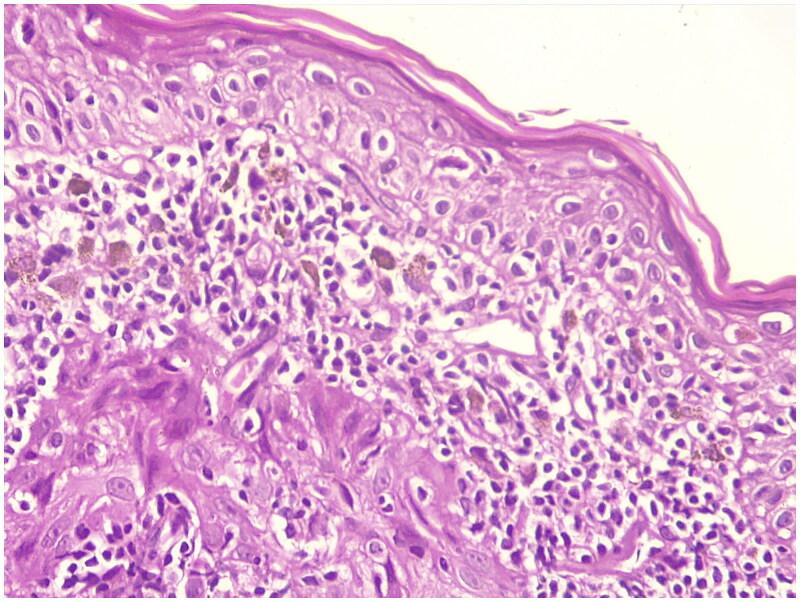

Lichen Planus is an inflammatory skin disease that has been reported to be associated with inflammatory diseases like Inflammatory Bowel Disease or with medication use such as sulfasalazine. We report a case of lichen planus in a 62-year-old patient with ulcerative colitis receiving sulfasalazine. Within three years of treatment, the patient developed an erythematous rash on her forehead and wrists, which gradually worsened and spread to her arms, forearms, neck, and upper back. Lichen planus was suspected and later confirmed through histopathological examination. Consequently, sulfasalazine was discontinued, leading to partial resolution of the skin lesions. Our case highlights the importance of a thorough patient interview, as the timeline of skin lesions in relation to medication use and disease activity.

扁平苔藓是一种炎症性皮肤病,据报道与炎症性肠病等炎症性疾病或柳氮磺胺吡啶等药物使用有关。我们报告一例62岁溃疡性结肠炎患者在接受柳氮磺胺吡啶治疗时发生扁平苔藓的病例。在治疗的三年内,患者前额和手腕出现红斑皮疹,逐渐加重并蔓延至手臂、前臂、颈部和上背部。怀疑为扁平苔藓,后来通过组织病理学检查得以确诊。因此,停用了柳氮磺胺吡啶,皮肤病变部分消退。我们的病例强调了全面患者访谈的重要性,因为皮肤病变的时间线与药物使用和疾病活动有关。